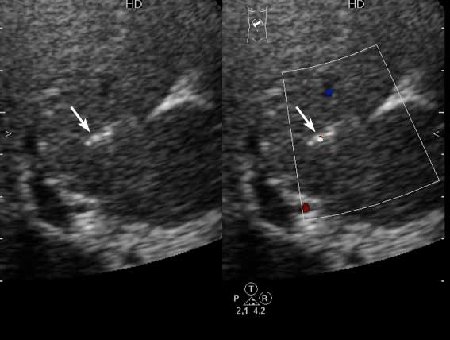

Внутрипротоковые гамартомы

Иногда встречается.

Получил данные за то, что, видимо, это мелкие конкременты в протоковой системе.

1) Эхогенные структуктуры дают твинклинг-артефакт (twinkling), характерный, например, для кальцийсодержащих образований.

2) Все пациенты, у которых наблюдалась подобная картина страдали ЖКБ, у всех был удален желчный пузырь.